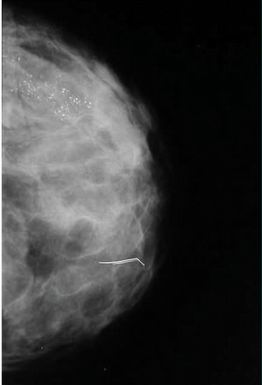

Kazuistika č.4

V HZQ jsou nepočitatelné, zrnité mikrokalcifikace v rozsahu asi 7

cm, s rozdílnou intra a interkorpuskulární denzitou, hodnoceny jako

maligní – dle histologie po exstirpaci

duktální karcinom

(ve VřQ technický artefakt)